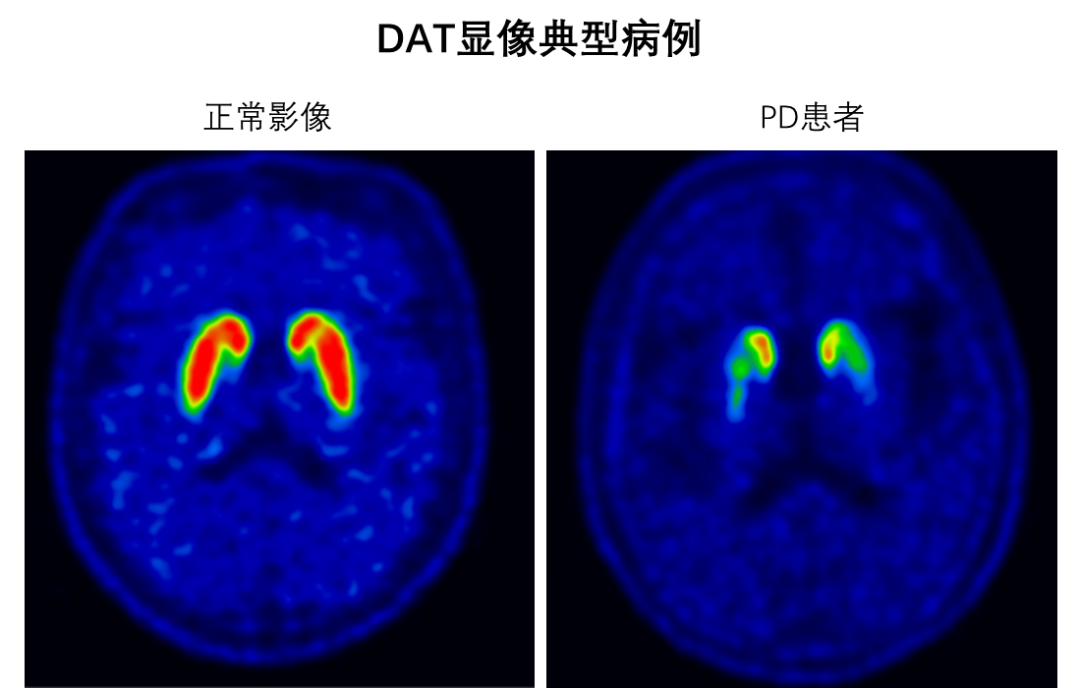

DAT显像则是查看负责运动协调的“多巴胺神经元”还剩多少。多巴胺神经元的减少是帕金森病的重要特征,通过DAT显像,医生可以准确评估多巴胺神经元的功能状态,帮助诊断帕金森病。